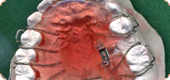

矯正治療の装置には、以下のような種類があります。

治療目的や歯の状態、生活環境によって治療法が異なります。